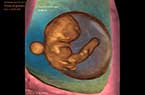

Embryon de 7 SA et 2 jours (LCC = 11.47 mm) - les premiers mouvements embryonnaires - Vidéo Embryon de 7 SA et 2 jours (LCC = 11.47 mm) - Imagerie 3D Embryon de 7 SA et 2 jours (LCC = 11.47 mm) - Les premiers mouvements embryonnaires - Vidéo pour YouTtube